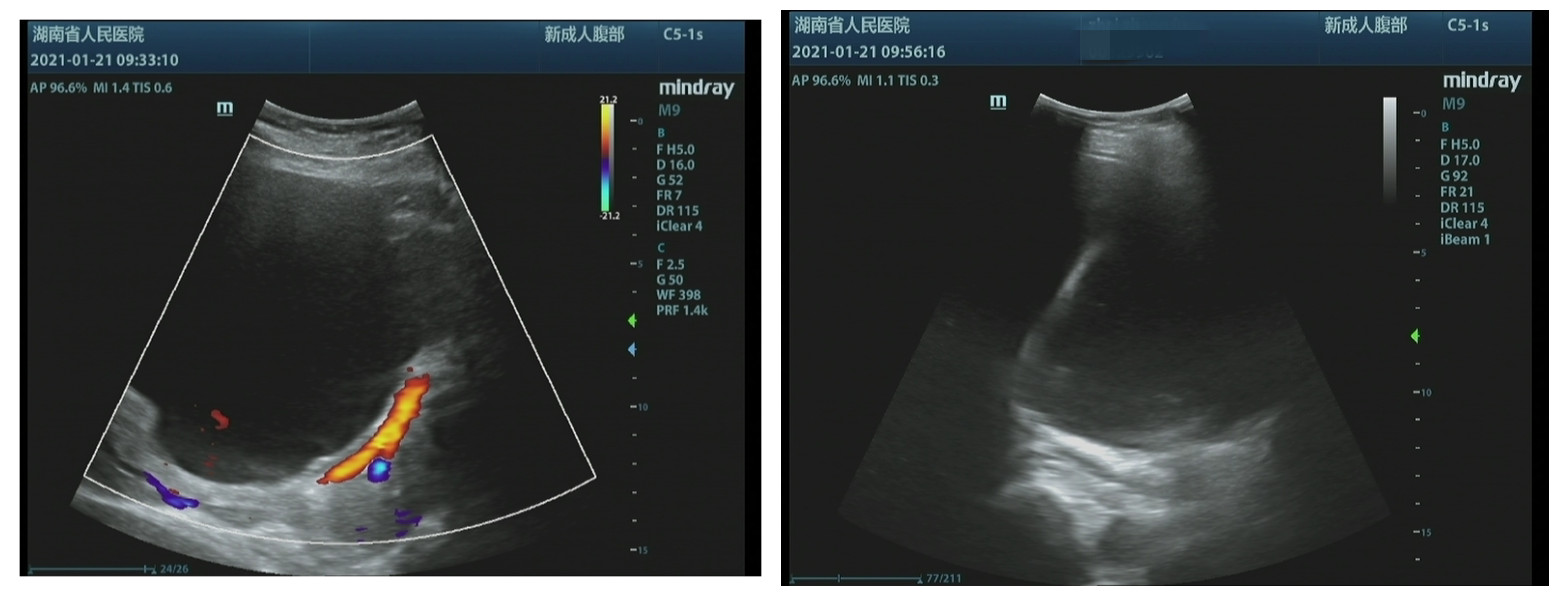

术前超声二科团队评价翟阿姨的最大的肝囊肿的内径是142x125x128mm,评估其内液体1086ml,相当于肝内有2斤多重的液体。

经过第一次穿刺引流24小时后,引流的大约800-900ml液体,引流后囊肿的内径缩小至31x25x28mm,评估其内液体仅剩9ml,大约99%的液体已经引流完毕,解除了对周围血管的压迫。

为了防止囊肿囊壁再次分泌囊液造成囊肿复查,超声二科危安主任团队为翟阿姨进一步注射了硬化剂(聚桂醇注射液)破坏囊肿囊壁以达到破坏囊肿活性的作用。